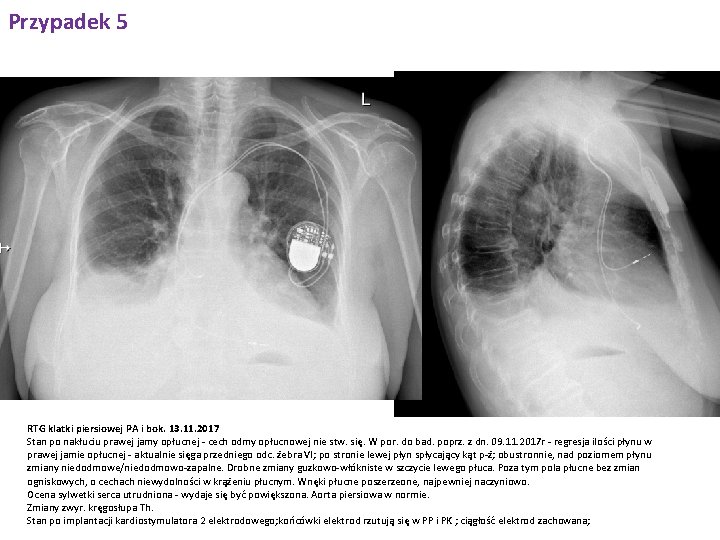

Przypadek 5 RTG klatki piersiowej PA i bok. 9. 11. 2017 Płyn w obu jamach opłucnej: więcej po stronie prawej - sięga przedniego odc V żebra; po stronie lewej sięga przedniego odc. VI żebra; obustronnie nad jego poziomem zmiany niedodmowe/niedodmowo-zapalne. Wzmożony rysunek naczyniowy i śródmiąższowy, o cechach niewydolności w krążeniu płucnym. Poza tym pola płucne bez uchwytnych zmian ogniskowych. Wnęki płucne poszerzeone, najpewniej naczyniowo. Sylwetka serca przesłonięta, nie do oceny. Aorta piersiowa w normie. Stan po implantacji kardiostymulatora 2 elektrodowego; końcówki elektrod rzutują się w PP i PK ; ciągłość elektrod zachowana; cech odmy opłucnowej nie stw. się.

Przypadek 5 RTG klatki piersiowej PA i bok. 13. 11. 2017 Stan po nakłuciu prawej jamy opłucnej - cech odmy opłucnowej nie stw. się. W por. do bad. poprz. z dn. 09. 11. 2017 r - regresja ilości płynu w prawej jamie opłucnej - aktualnie sięga przedniego odc. żebra VI; po stronie lewej płyn spłycający kąt p-ż; obustronnie, nad poziomem płynu zmiany niedodmowe/niedodmowo-zapalne. Drobne zmiany guzkowo-włókniste w szczycie lewego płuca. Poza tym pola płucne bez zmian ogniskowych, o cechach niewydolności w krążeniu płucnym. Wnęki płucne poszerzeone, najpewniej naczyniowo. Ocena sylwetki serca utrudniona - wydaje się być powiększona. Aorta piersiowa w normie. Zmiany zwyr. kręgosłupa Th. Stan po implantacji kardiostymulatora 2 elektrodowego; końcówki elektrod rzutują się w PP i PK ; ciągłość elektrod zachowana;